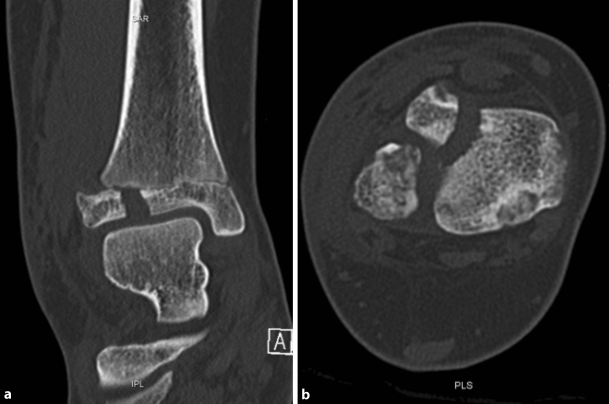

An exemplary case of a 14-year-old patient with a surgically treated Tillaux fracture is presented in Figs. 2 to 5 (Fig. 2a, b, X‑ray; Fig. 3a, b, CT scan; Fig. 4a, b, X‑ray after open reduction and screw fixation; Fig. 5a, b, X‑ray in two planes after screw removal).

Fig. 3

CT scan, coronal (a) and axial plane (b) of a Tillaux fracture in a 14-year-old patient

Bild vergrößern